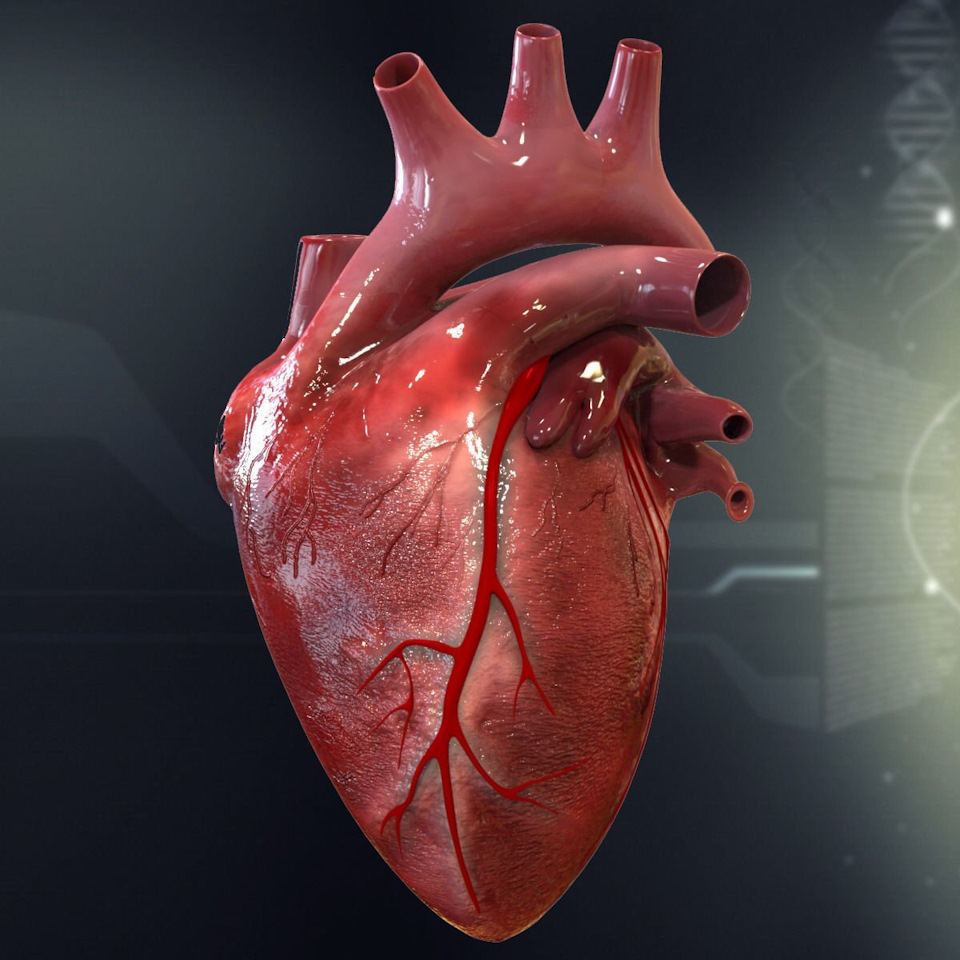

Анатомия здорового сердца: фотографии и иллюстрации